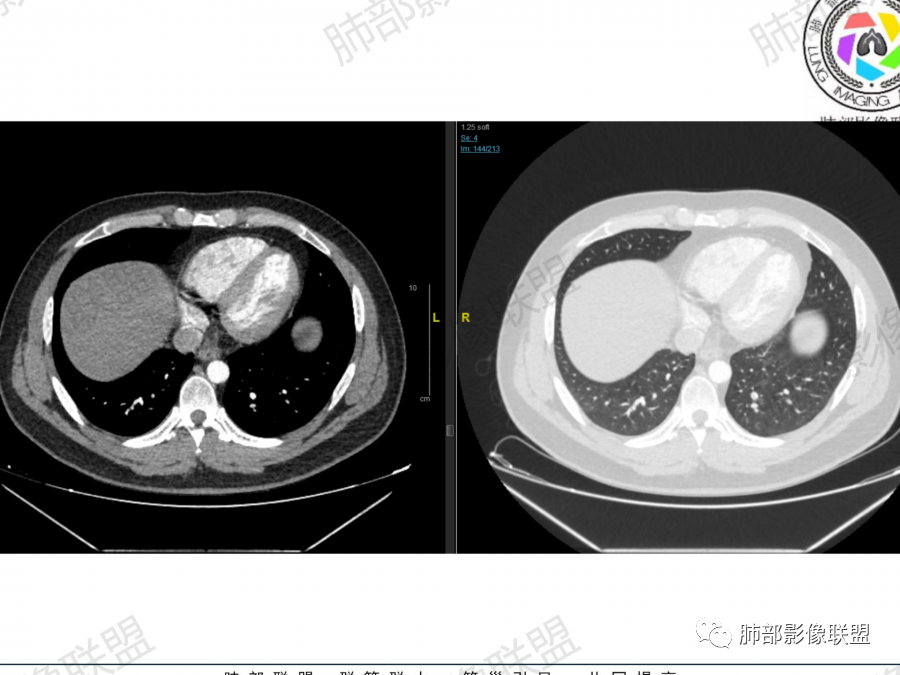

2、右肺多发结节影,大者位于右肺上叶尖段,内可见空洞,空洞内壁欠规整,内可见分隔,余结节位于胸膜下、结节大小不等、形态相近,强化均匀,内部可见血管穿行,血管及支气管走行自然。结合临床及影像,符合隐球病。

2、隐球菌感染有时相性,初期的隐球菌感染周围有晕征,晕从多变少,或包裹,或吸收,结节实性区可迅速变大,后期(慢性期)的隐球菌周围无明显晕征,边界较清楚。本例病变发病一月, 为后期,晕征不明显。

总之,隐球菌卫星灶形态相似、可位于病变周围及远侧肺。与结核球的鉴别是:结核卫星灶、多形、多灶, 往往位于主病灶周围。本例卫星灶与“蘑菇兄弟”在右肺下叶,有提示作用。